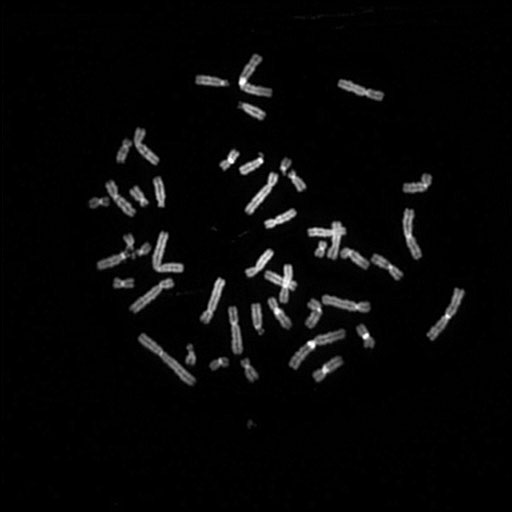

081 C